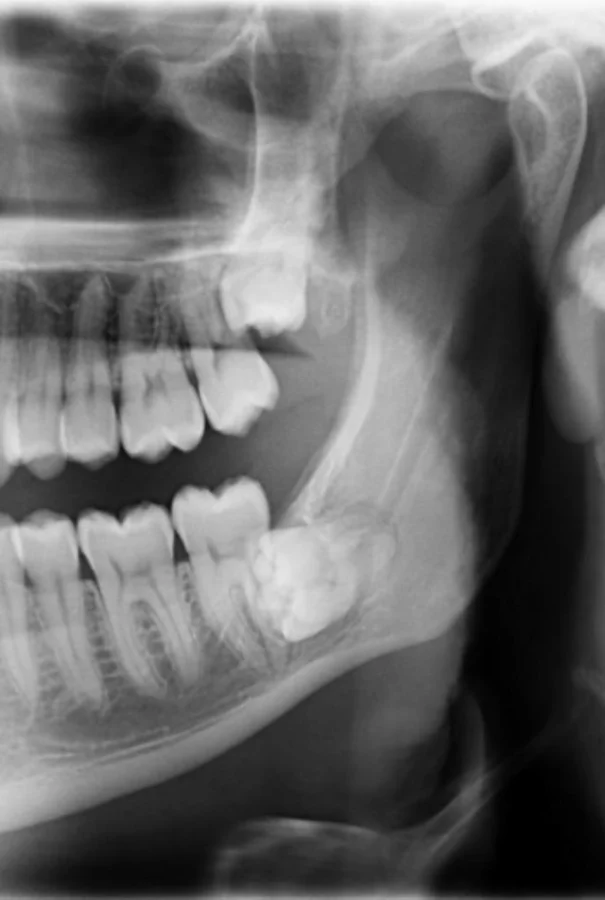

19. «Рентгеновский снимок зубов моего шестилетнего ребёнка»